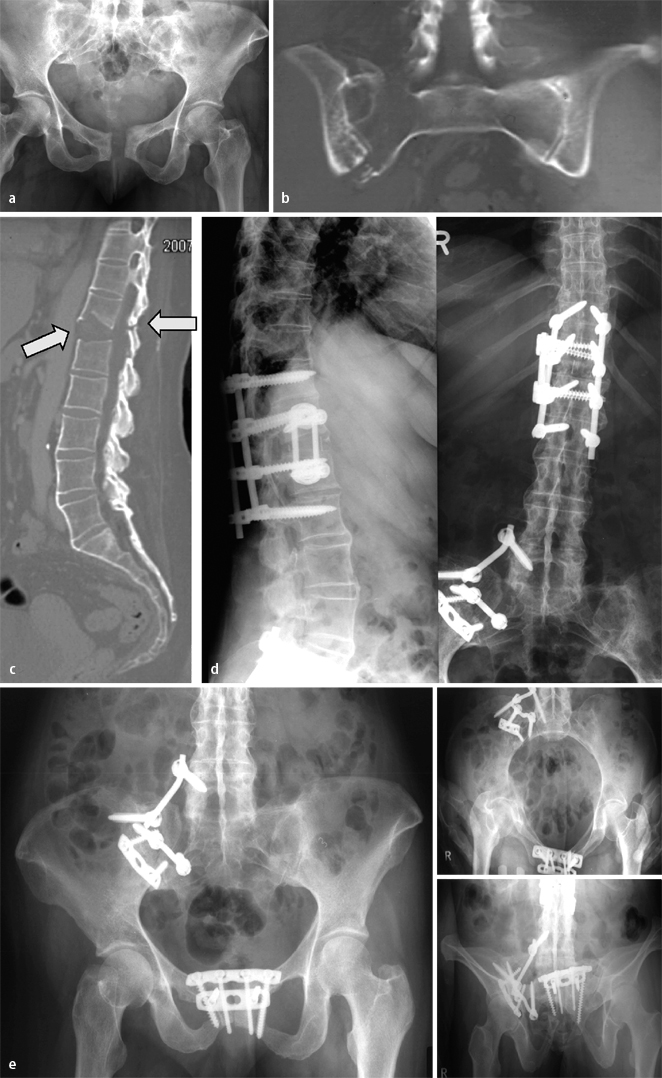

Ein valider Beleg der erreichten Behandlungsqualität (z. B. intraoperative Reposition, korrekte Implantatlage) ist nicht allein wegen potenzieller späterer juristischer Implikationen, sondern v. a. zur Sicherung des klinisch-wissenschaftlichen Zusammenhangs zwischen Repositionsresultat und Outcome relevant. Zwar wird die Wertigkeit einer postoperativen CT-Kontrolle noch kontrovers diskutiert [13], nicht zuletzt weil der bisherige Goldstandard der postoperativen Bildgebung die Standardröntgenuntersuchung darstellt [4, 6] und biologische Parameter der jeweiligen Verletzung und Versorgung hiermit nicht detektiert werden können, doch gibt diese Form der postoperativen Bilddokumentation dem Operateur ein gutes Instrument an die Hand, residuale Fehlstellungen nach Rekonstruktion und die adäquate und gesichert extraartikuläre Implantatlage zu dokumentieren, somit „Schwachstellen“ der spezifischen Versorgung nachzuweisen (Abb. 8 c,d). Hieraus kann neben einem persönlichen Lerneffekt auch eine Indikation für eine operative Frührevision abgeleitet werden. Moderne Formen der intraoperativen Bildgebung (z. B. 3D-Bildverstärker, Abb. 8 c) sind hierbei von Vorteil, da bei mittlerweile guter Abbildungsqualität und limitiertem Zeitaufwand dem Operateur die Chance geboten wird, ggf. intraoperativ weitere Nachkorrekturen vorzunehmen, also die postoperative CT-Untersuchung und einen evtl. Zweiteingriff entbehrlich zu machen. Der Vergleich zwischen der intraoperativen 3D-Bildverstärkung und einem postoperativen Standard-CT mit multiplanerer Rekonstruktion scheint dies zu untermauern (Abb. 8 d–f).

Fall 7, 52-jähriger Polytraumapatient (AO 62A2.3), a,b erhebliche Impressionszonen und osteochondrale Frakturen im Pfannendachbereich, c intraoperative Kontrolle von Reposition und Implantatlage nach ORIF mit 3D-Bildverstärker, d Entfernung der markierten Zugschraube und nochmalige 3D-Bildverstärker-Kontrolle, e,f postoperatives a.-p. Röntgenbild und 2D-Rekonstruktion nach CT, weitere Erläuterungen s. Kasuistik

Fall 7

Der 52-jährige männliche Polytraumapatient (AO 62A2.3) wies erhebliche Impressionszonen und osteochondrale Frakturen im Pfannendachbereich auf.

Nach ORIF über einen erweiterten dorsalen Zugang mit Trochanter-Flip-Osteotomie wurden die Reposition und die Implantatlage intraoperativ mit dem 3D-Bildverstärker kontrolliert. Die dabei identifizierte „Schwachstelle“ der operativen Versorgung wurde in gleicher Sitzung behoben und das Ergebnis erneut intraoperativ kontrolliert.

Die postoperative Röntgenuntersuchung und CT-Rekonstruktion bestätigten den Befund der intraoperativen Kontrollaufnahme (Abb. 8).